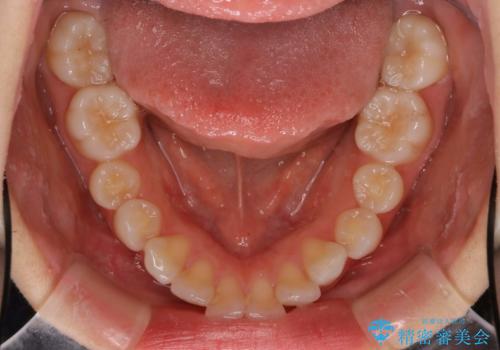

インビザラインで出っ歯を改善する 抜歯をしないinvisalign治療

- 非抜歯・遠心移動による前突の改善をマウスピースにて計画した。

非抜歯矯正の場合、大きく前歯を下げることはできませんが、奥歯の遠心移動や歯のサイズダウンにより歯軸を立て、見かけ上の出っ歯感をある程度改善することができます。